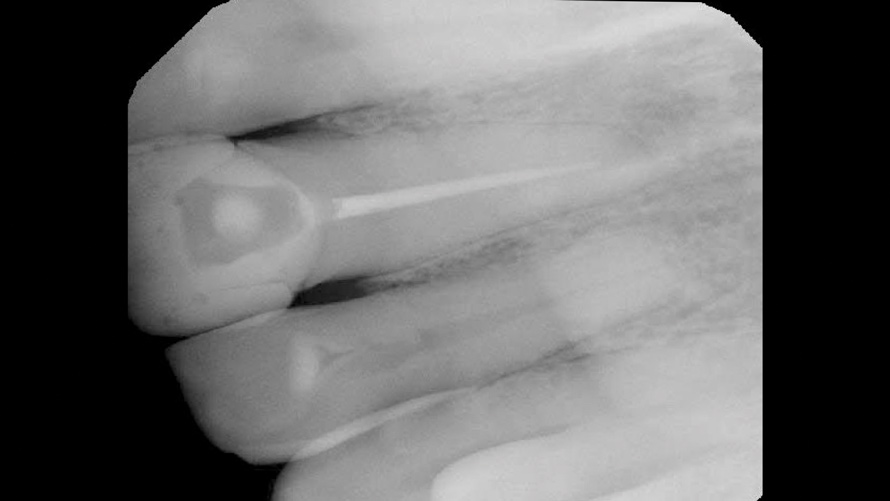

In the second case, a preoperative periapical radiographic examination revealed that the patient had previously undergone nonsurgical root canal therapy and that the existing root-filling material stopped 3 mm to 4 mm short of the apex (Figure 4). Further examination revealed an intact lamina dura and normal bone trabeculation. Under high-power microscope magnification, the existing root canal sealer appeared to be the cause of the intrinsic staining; therefore, it was deemed necessary to re-treat and refill the existing root canal.

(4.) Case 2: Preoperative radiograph of the maxillary left central incisor, demonstrating existing nonsurgical root canal therapy.

Figure 4